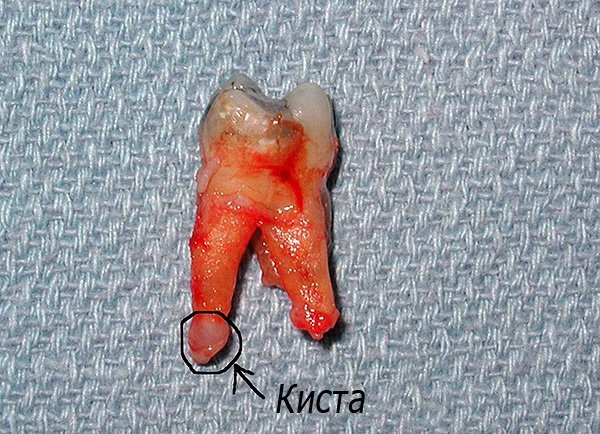

A foto abaixo mostra um exemplo de dente removido com cistos nas raízes:

O que é um cisto dentário? O cisto radicular do dente é uma neoplasia localizada principalmente no ápice da raiz e é uma espécie de cápsula, cujo interior da concha contém líquido. Sob certas condições patológicas, o cisto é capaz de crescer com o tempo, aumentando de tamanho.